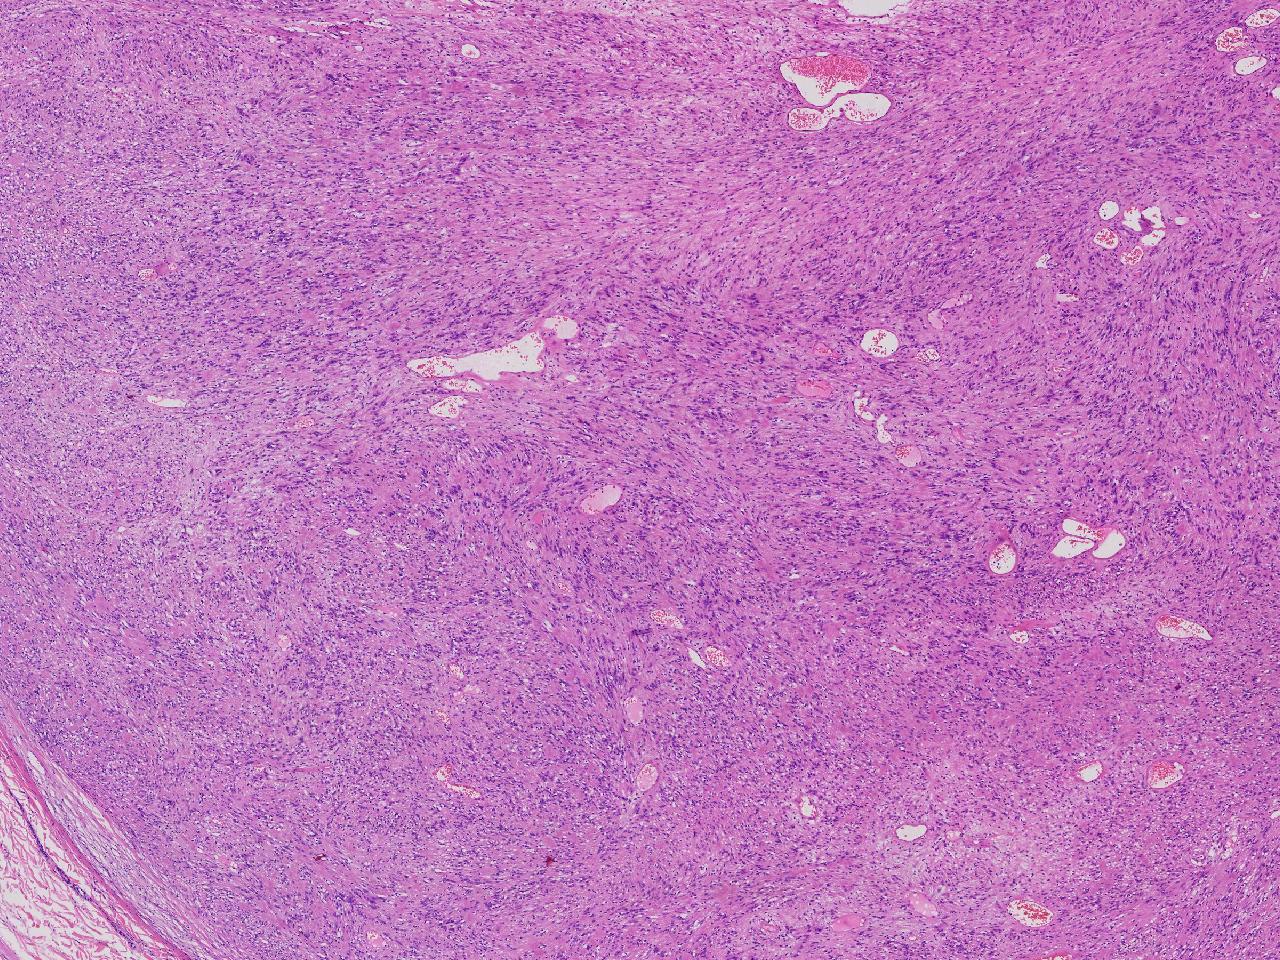

血管平滑肌瘤? 其他?

性别

女

年龄

76岁

临床诊断

右侧腰臀部皮下肿物

一般病史

右侧腰臀部皮下肿物1年余,无明显不适,逐渐增大。

标本名称

大体所见

卵圆形肿物一个,直径1.6厘米,上附皮肤。肿物切面灰黄实性,质中等。

考虑:结节性筋膜炎

神经鞘瘤。

建议除外平滑肌瘤,做IHC是更好的鉴别方式